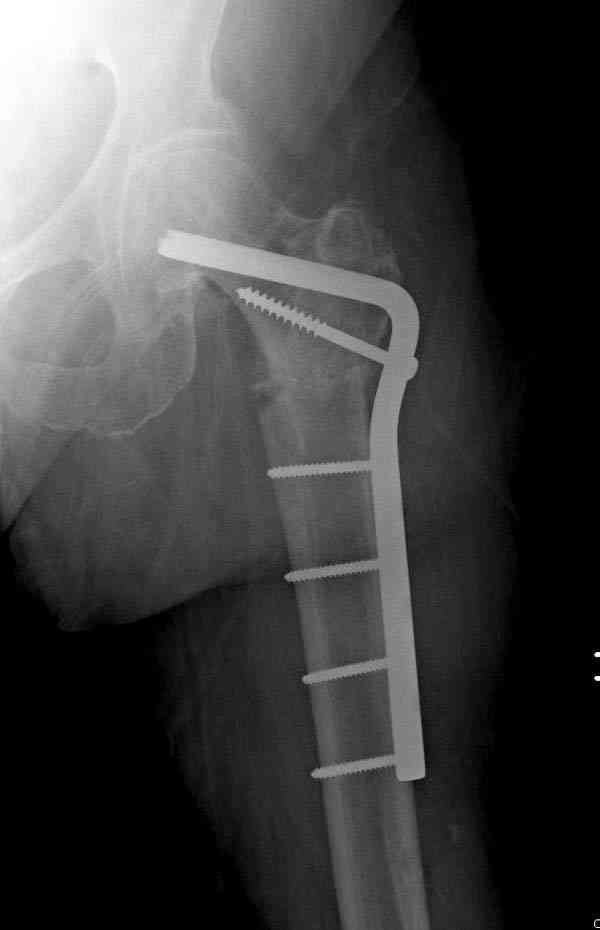

Не стали усложнять интрамедуллярным вариантом коррекции, легче контролировать коррекцию пластиной, поэтому сделали операцию 95 градусной Blade Plate, разогнув до 110 градусов.

Надеемся на успех, потому что до введения пластины дефект от импланта забили костной стружкой и удалось создать компрессию между отломками, максимальную для импланта (150 кило/паунд). Сделана дополнительная костная пластика и за счет измененного угла пластины устранено укорочение конечности.